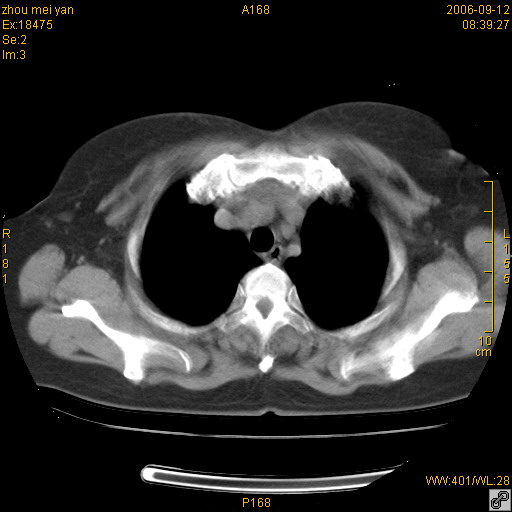

患者、女、55岁。因心率失常住院检查ct发现胸部多发结节。腹部b超肝、胆、胰、脾、肾、子宫附件未见异常。无结核病史,无粉尘接触史。请大家来会诊。谢谢!

病变位于胸膜,多发结节,边界清楚,内见小结节状钙化。其它未见异常。

双侧胸膜多发结节,形态不规则,边缘较清楚,每一个结节中心似乎都有钙化点的特征,与胸膜广基相切。临床无结核病史,无粉尘接触史。

影像表现十分有特点:双侧肋胸膜及膈胸膜广泛散在分布大小在2至6mm左右,较大病灶中心可见钙化。

考虑恶性胸膜间皮瘤可能性大,病灶位于胸膜,以宽基地与胸膜相连,呈结节样改变,部分病灶内可见点状钙化影。请各位老师多多指导!

双侧肋胸膜及膈胸膜广泛散在分布大小不等结节影,较大病灶中心可见钙化。